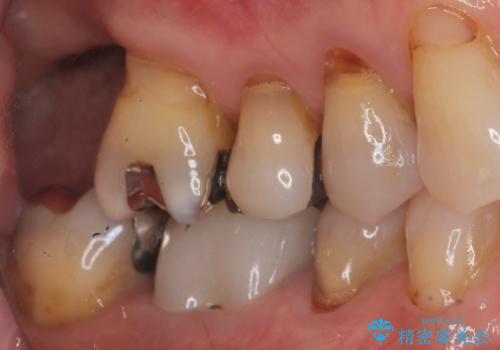

今回の治療では、まず重度歯周病の右上6番を慎重に抜歯し、その直後に6番と、すでに欠損していた7番の部分に、合わせて2本のインプラントを埋入しました。

抜歯即時埋入(6番): 抜歯と同時にインプラントを埋入することで、骨の吸収を最小限に抑え、治療期間を大幅に短縮しました。

7番のインプラント埋入: 6番と同時に埋入することで、治癒期間を一括で管理でき、効率的に治療を進めることができました。

その後、インプラントと骨がしっかりと結合するのを待ってから、最終的な被せ物(クラウン)を装着。これにより、重度歯周病で失われた2本の奥歯を、強固で安定したインプラントで再建。以前のような不安なく、しっかりと噛める快適な食生活を取り戻していただけました。